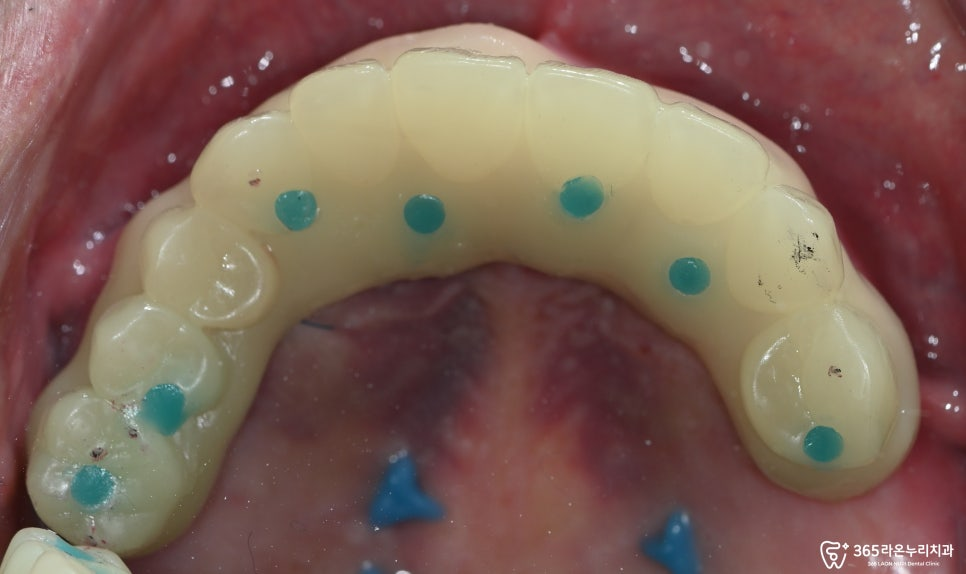

1차 임시치아를 세팅 후

체크와 적응기간을 가진 후

다시 더 심미적으로

사용할 수 있도록

2025.3.12

2차 임시치아는 잇몸색도

표현을 해드렸는데요.

좀 더 자연스러운 모습을

확인할 수 있었습니다.

그리고 위턱과 아래턱이 맞닿는

대합치와 원할히 저작할 수 있도록

높이도 잘 체크해 드렸습니다.